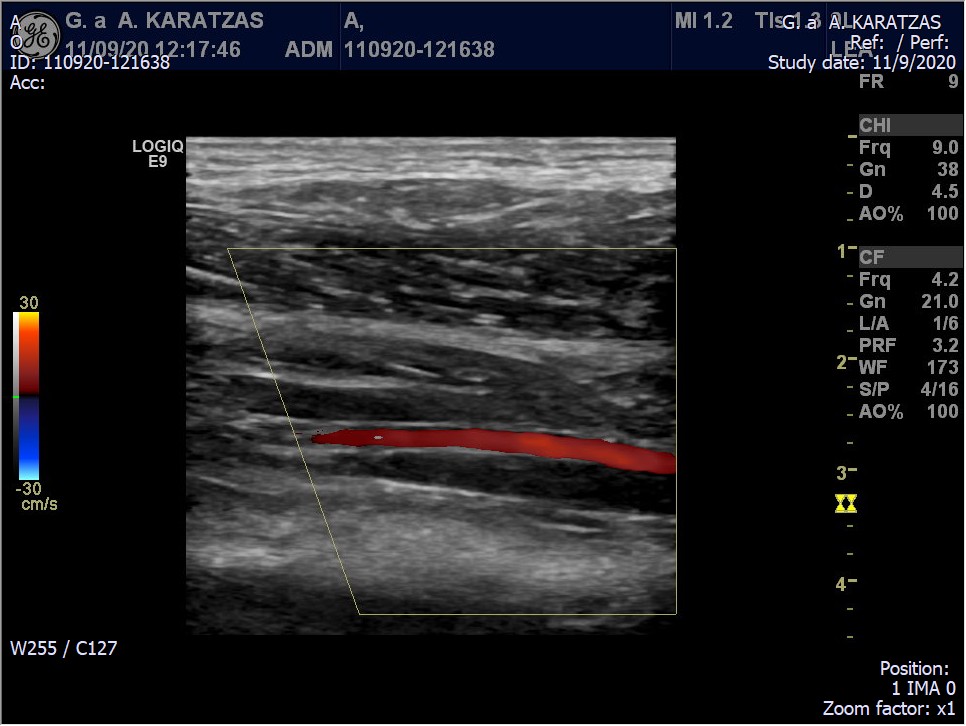

Το έγχρωμο υπερηχογράφημα των αγγείων (Triplex αγείων) είναι μια εξέταση με υψηλή ακρίβεια στην εκτίμηση της βατότητας και της διαμέτρου των αγγείων. Επιτρέπει τον έλεγχο των περισσότερων αγγείων του σώματος. Εξαίρεση αποτελούν αγγεία η απεικόνιση των οποίων εμποδίζεται από παρεμβαλλόμενο αέρα ή οστά, όπως η θωρακική αορτή (τμήμα της ανιούσας θωρακικής αορτής μπορεί να ελεγχθεί από καρδιολόγους με το υπερηχογράφημα καρδιάς) και τα ενδοκράνια αγγεία (τμήμα τους μπορεί να ελεγχθεί με ειδική τεχνική από εξειδικευμένους νευρολόγους). Τα triplex αγγείων που πραγματοποιούνται συνήθως είναι τα εξής:

Triplex αρτηριών κάτω άκρων-λαγονίων αρτηριών:

Πρόκειται για πολύ σημαντική εξέταση στον έλεγχο ασθενών με συμπτώματα που υποδηλώνουν στένωση των αρτηριών των κάτω άκρων, όπως διαλείπουσα χωλότητα και άλγος στα κάτω άκρα.  Μπορεί να αναδείξει με εξαιρετική ακρίβεια στενώσεις και αποφράξεις στις αρτηρίες των κάτω άκρων, από τις λαγόνιες έως και τις κνημιαίες αρτηρίες. Ο αγγειογραφικός έλεγχος (αξονική, μαγνητική ή ψηφιακή αγγειογραφία) συνήθως χρειάζεται μόνο σε ασθενείς που είναι υποψήφιοι για επέμβαση.

Triplex φλεβών κάτω άκρων:

Είναι η εξέταση εκλογής για ανάδειξη θρόμβωσης ή ανεπάρκειας των επιπολής (επιφανειακές) και εν τω βάθει φλεβών των κάτω άκρων. Πραγματοποιείται συνήθως σε ασθενείς με οίδημα και/ή άλγος στα κάτω άκρα. Δίνει τη δυνατότητα ανάδειξης θρόμβωσης ακόμα και στα αγγεία κάτωθεν του γόνατος με μεγάλη ακρίβεια και έχει αντικαταστήσει την ψηφιακή φλεβογραφία που πραγματοποιούταν στο παρελθόν. Συγχρόνως βοηθάει να εκτιμηθεί ο βαθμός ανεπάρκειας του εν τω βάθει και επιπολής φλεβικού συστήματος και είναι απαραίτητη εξέταση για τον σχεδιασμό πριν από επεμβάσεις για τη φλεβική ανεπάρκεια (χειρουργίο, laser, σκληροθεραπεία κλπ).